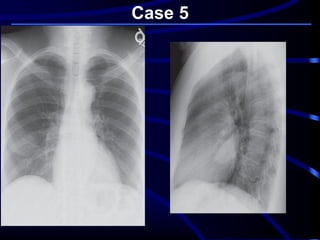

Case 5

A 68-year-old asymptomatic

nonsmoking woman underwent

preoperative screening chest

radiography in preparation for a total

knee arthroplasty. The radiographic

findings prompted subsequent chest

CT

Where is this lesion MOST

LIKELY located?

A. Lung parenchyma.

B. Mediastinum.

C. Pleura.

D. Chest wall..

What is the MOST LIKELY

diagnosis?

A. Primary lung cancer.

B. Chest wall chondrosarcoma.

C. Pseudotumor or vanishing

tumor of the pleura.

D. Localized fibrous tumor of the

pleura..

..pleura